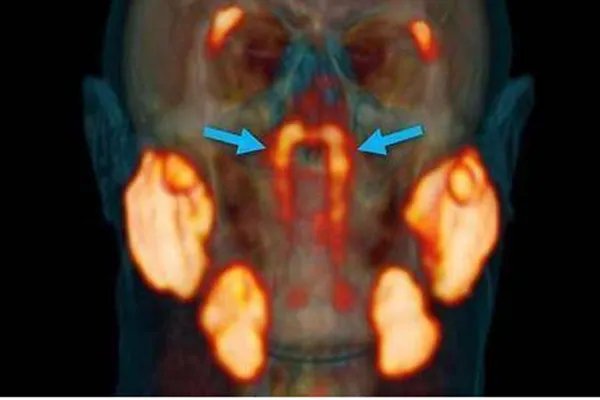

01、科学家在人体内发现未知新器官。10月20日外媒报道,荷兰的一个研究癌症的研究在人体内发现了新的器官,该器官位于鼻咽里面咽鼓管隆凸的软骨上 ,据研究人员称这是一种腺体,以前人们从没有发现过。

因为其生在的部位,所以专家们给它命名为隆凸唾液腺,人类在之前只有发现了三大唾液腺分别是腮腺、颌下腺和舌下腺,现在发现这个唾液腺很可能会成为第四大,具体还需要专家们做出详细解释。